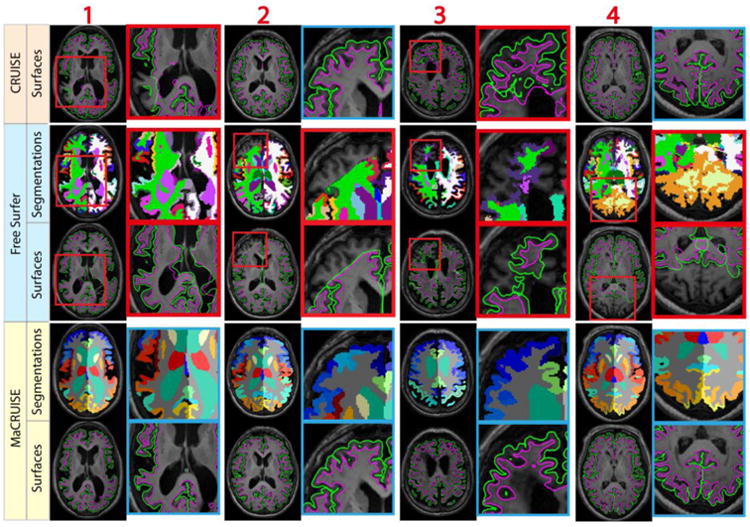

Mean ASD between MaCRUISE and the benchmark algorithms are generally around or smaller than 0.5 mm (Figure 10a). However, there are four images (marked using red numbers 1 through 4) that are located outside of a margin of 2.5 standard deviations. These large surface distances indicate that at least one of the methods failed with these images. For the ventricle volumes, a strong linear correlation was found except in seven outlier volumes (marked using green numbers 4 through 11) (Figure 10b). Thus, a total of 11 failed volumes were automatically detected. The segmentations and surfaces of the failures for these subjects are shown in Figure 11 (red outliers) and Figure 12 (green outliers). The global failures (in the red rectangles) occur in all 11 volumes for FreeSurfer and in two volumes for CRUISE. In contrast, we do not find any global failures from MaCRUISE. Therefore, none of the 11 failures are attributable to MaCRUISE. To complete the analysis, we visually inspected the surfaces and segmentations for the remaining 189 volumes and did not find any global failures for either MaCRUISE or the benchmark algorithms.

Fig. 11.

The four outliers from surface distance analysis are shown. Both whole brain segmentations and cortical surfaces on axial slices are provided. The areas in red rectangles show the global failures in FreeSurfer whereas MaCRUISE did not exhibit any such failures.

Fig. 12.

The seven outliers from inconsistent lateral ventricle size are shown. Both whole brain segmentations and cortical surfaces on axial slices are provided. The areas in red rectangles show the global failures while the areas in yellow rectangles show the local inaccurate surfaces. MaCRUISE did not exhibit such failures in any images.